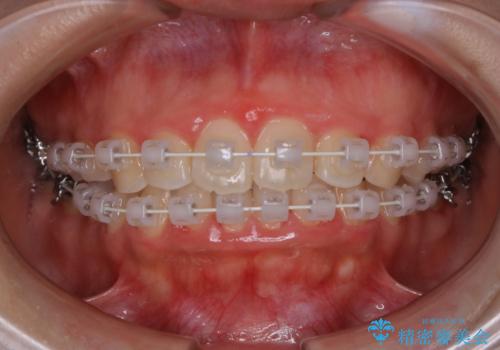

- 矯正装置

- ワイヤー審美装置

- 4年ほど前から地元の歯科医院にてインビザライン治療を行っていたが、引っ越し後に通いづらくなってしまったため、治療が途中で止まってしまっているとの事で来院されました。性格的にインビザラインの継続した使用が難しいとのことで、ワイヤー装置にて最終仕上げを行いました。

インビザラインは20時間以上の装着を厳守して頂くことで治療効果が期待できる治療となります。固定式のワイヤー装置に切り替えることで短期間で歯並びを整えることができ、大変喜んでいただけました。